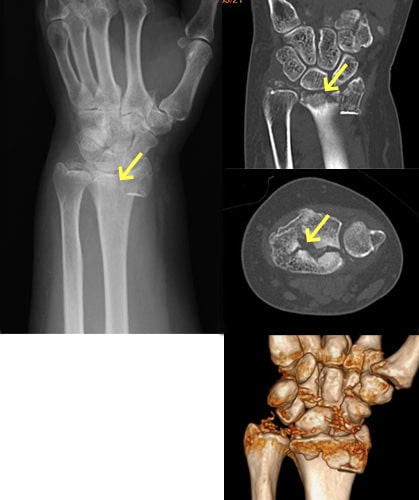

舟状骨骨折

舟状骨骨折写真

舟状骨骨折後偽関節

舟状骨骨折術後写真

骨移植併用内固定術後

原因

スポーツや事故で手をついて転倒することで生じます。舟状骨骨折は通常のレントゲン写真で分かりづらいことも多く、専門医でないと見落とすこともあります。手首の痛みが残る場合は舟状骨骨折を疑って多くの方向からレントゲン写真を撮ったり、CT撮影をする必要があります。

症状

腫れや痛みなどの症状が軽いため、整形外科への受診が遅れたり、手首の捻挫や打撲として診断されてしまっていることがあります。

治療方針

直後で骨折部のズレが少なければギプスで治療することも可能です。しかし、骨折部のズレが大きければ手術となります。また、長期間放置されて骨折部が治らないままとなったり(偽関節)、それに伴って関節の軟骨が摩耗した場合(変形性手関節症)は侵襲の大きな手術が必要となります。